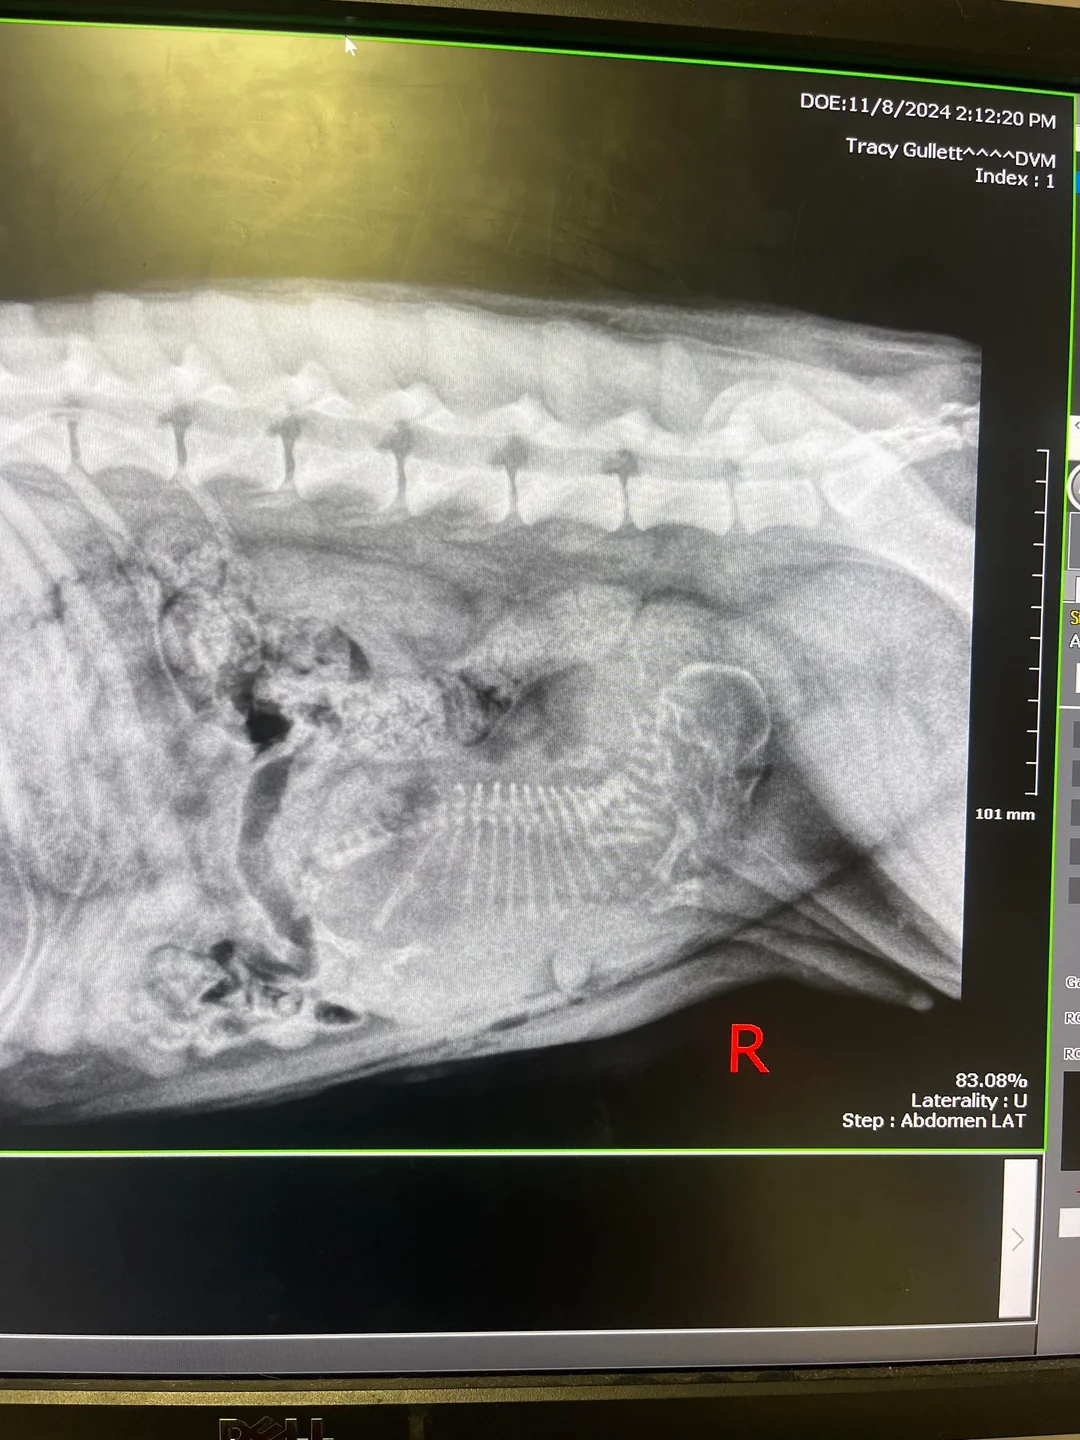

During the operation, the veterinary team encountered a surprise. After making the first incision, they discovered that Salem was pregnant.

Haley took to Reddit to express her astonishment: “Found out at [the spay appointment] that my new rescue dog is pregnant with one puppy,” she shared.

After discussing the unexpected circumstances with her vet, Haley learned that since Salem was carrying just one puppy, stopping the pregnancy could lead to complications. Taking the advice of her vet, she decided to let the pregnancy progress.

Pregnancies involving just one puppy, known as singleton pregnancies, are rare. They can result from various causes, including low ovulation, fertilization issues, or specific genetic traits.

Singleton pregnancies carry specific risks. A single puppy may grow larger than anticipated, heightening the risk of complications during birth.